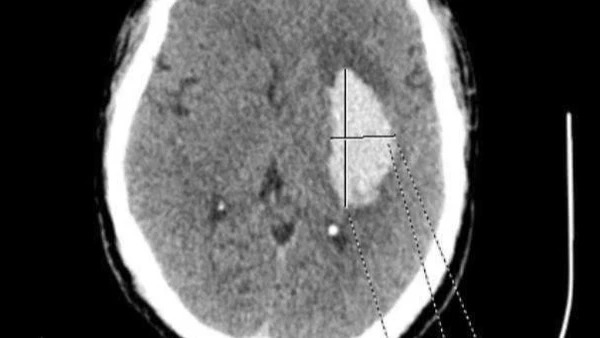

Hình ảnh phim chụp khối u của bệnh nhân trước khi phẫu thuật.